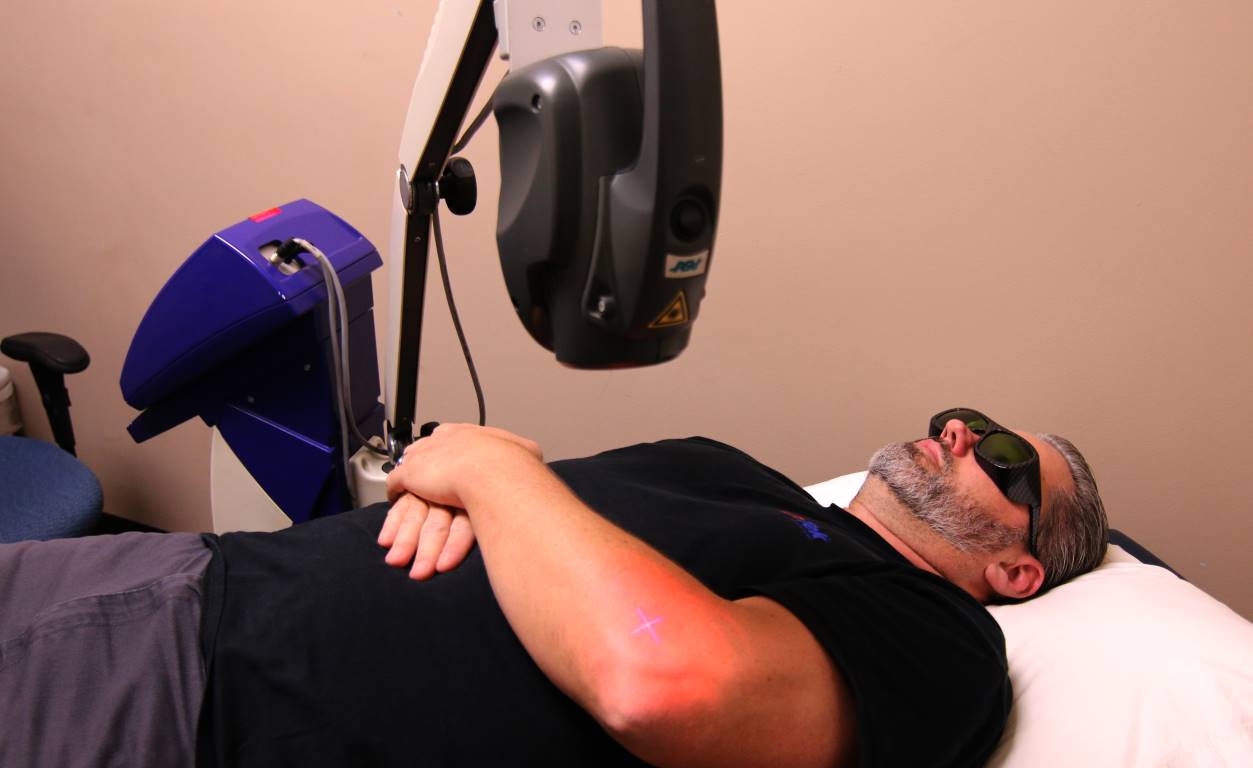

Class IV Cold Laser

Cold laser therapy is a treatment that utilizes specific wavelengths of light to interact with tissue and help accelerate your healing process. Cold laser treatment can be used on people suffering from acute and chronic conditions in order to eliminate pain and swelling, increase functionality, and reduce spasms.

Our friendly and educated providers will hold the cold laser and place it directly on the injured area for a few minutes. At this time, the non-thermal photons of lights will be emitted from the laser and pass through the skin layers. The light has the ability to penetrate two to five centimeters below the skin at 90 mw and 830 nm.

When the light energy passes through your skin and reaches the injured area, the energy is absorbed and interacts with the light-sensitive elements in your cells. When cells absorb this light energy, it will assist with normalizing damaged or injured tissue, reducing pain, inflammation, edema, and overall healing time.

Our entire staff wants to assist you in getting to the root of your problem as quickly as possible. We understand the many benefits of cold laser therapy and will always go above and beyond for you. If you ever have any questions before, during, or after your therapy, we are always willing to answer them. We want you to feel completely comfortable throughout the entire process.

We utilize a laser by MLS cutting edge, MIX 5.

If you have any questions regarding cold laser therapy, contact us today at (949) 454-8811.